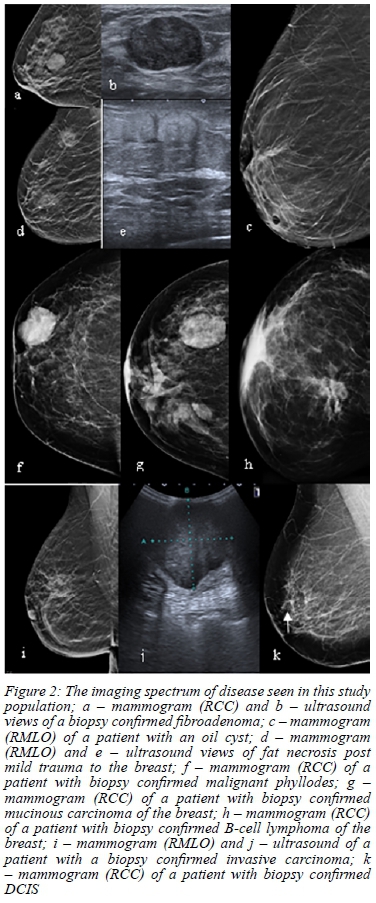

The imaging spectrum of disease within the study population is illustrated in Figure 2.

Some other malignant lesions seen were malignant phyl-lodes, lymphoma and mucinous breast carcinoma - lesions which can mimic benign disease clinically as well as on imaging. They present as well-defined masses clinically and well-circumscribed masses on both mammogram and ultrasound. It is in these cases that histology becomes very important.